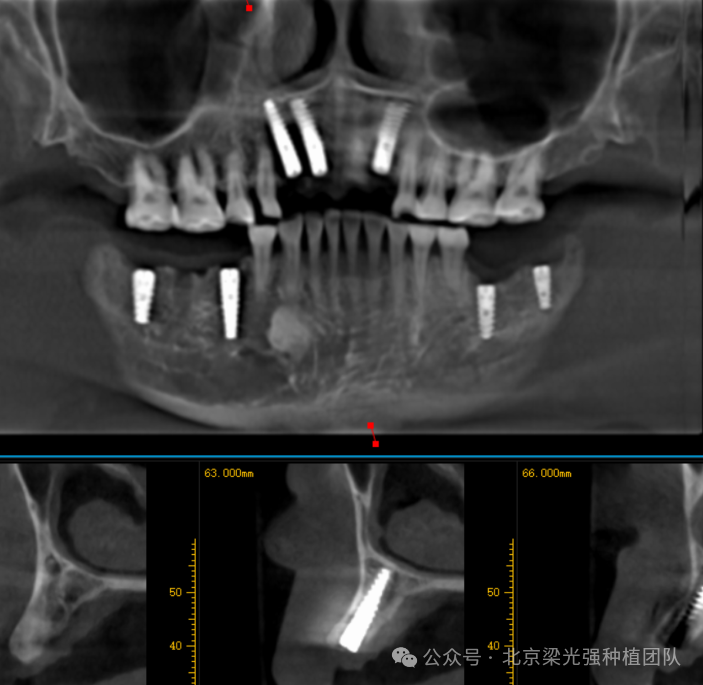

术前CBCT:

术后CBCT:

图片